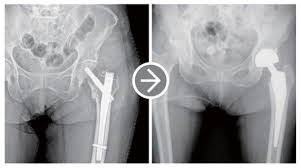

고관절 수술(고관절 전치환술, 인공관절 치환술 등)은 말기 관절염, 골절, 골수 괴사 등 다양한 원인으로 시행됩니다. 수술 후 회복 기간은 수술 방식, 환자 상태, 재활 병행 여부에 따라 다르지만, 일반적으로 3개월~1년 정도 소요됩니다. 본 포스트에서는 수술 종류, 회복 단계, 재활 프로그램, 주의사항, 일상 복귀 팁을 2,500자 이상으로 상세하게 안내합니다.

- 고관절 전치환술(Total Hip Arthroplasty, THA): 골관절염이나 류마티스 관절염, 골절 등에 널리 사용되는 방식으로, 관절 전체를 인공 관절로 교체합니다.

- 반치환술(Hemiarthroplasty): 대퇴골 두부 골절 등 특정 상황에 고관절 반만 인공으로 바꿔주는 방식입니다.

- 정기 검진: 엑스레이 또는 CT로 인공관절의 상태 확인